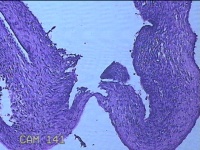

右侧卵巢囊肿

性别

女

年龄

临床诊断

一般病史

下腹痛3天。

标本名称

大体所见

灰白暗红色囊壁样组织2.5x1.5x0.3cm一块,表面糜烂,因已切开,囊内容物已流失,囊壁厚0.1cm。

图1